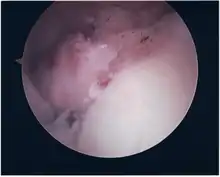

Twelve varieties of SLAP lesion have been described, with initial diagnosis by MRI or arthrography and confirmation by direct arthroscopy.[6]

- Type I - 11 o'clock to 1 o'clock. Fraying of the superior labrum, though it remains firmly attached to the glenoid rim.

- Type II - 11 o'clock to 1 o'clock. Tear of biceps labral complex

- Type IIa - 11 o'clock to 3 o'clock. Primarily anterior.

- Type IIb - 9 o'clock to 11 o'clock. Primarily posterior.

- Type IIc - 9 o'clock to 3 o'clock. Combined anterior and posterior.

- Type III - 11 o'clock to 3 o'clock. Bucket-handle tears of the superior portion of the labrum without involvement of the biceps brachii (long head) attachment.

- Type IV - 11 o'clock to 1 o'clock. Bucket-handle tears of the superior portion of the labrum extending into the biceps tendon.

- Type V - 11 o'clock to 5 o'clock. Anteroinferior Bankart lesion that extends upward to include a separation of the biceps tendon.

- Type VI - 11 o'clock to 1 o'clock. Unstable radial flap tears associated with separation of the biceps anchor.

- Type VII - 11 o'clock to 3 o'clock. Anterior extension of the SLAP lesion beneath the middle glenohumeral ligament.

- Type VIII - 7 o'clock to 1 o'clock. Extension into posterior labrum, more extension than type IIb.

- Type IX - 7 o'clock to 5 o'clock. Circumferentially abnormal labrum.

- Type X - 11 o'clock to at least 1 o'clock. Extension into rotator cuff interval.

- Type XI - Extends into superior glenohumeral ligament

- Type XII - Superior labrum anterior cuff lesion